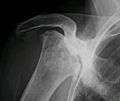

X-ray images of avascular necrosis in the early stages usually appear normal. In later stages it appears relatively more radio-opaque due to the nearby living bone becoming resorbed secondary to reactive hyperaemia.[1] The necrotic bone itself does not show increased radiographic opacity, as dead bone cannot undergo bone resorption which is carried out by living osteoclasts.[1] Late radiographic signs also include a radiolucency area following the collapse of subchondral bone (crescent sign) and ringed regions of radiodensity resulting from saponification and calcification of marrow fat following medullary infarcts.

Radiography of total avascular necrosis of right humeral head. Woman of 81 years old with diabetes of long evolution.